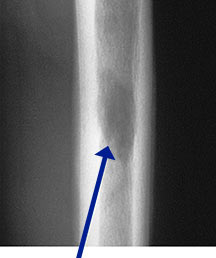

- May arise from any bone and any site within a bone (epiphyseal, metaphyseal, diaphyseal)

- Radiographically variable appearance: may appear benign (geographic) or malignant (permeative or moth eaten)

Sites:

- Flat Bones (most common—70%)

- Femur